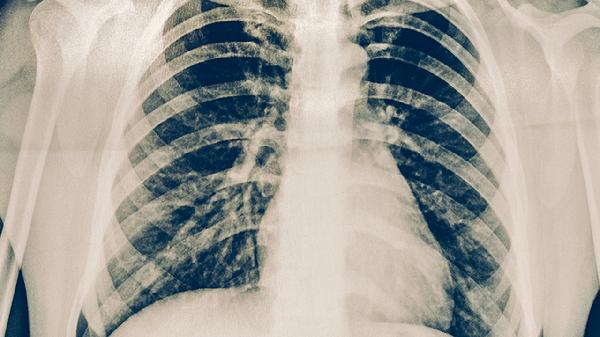

骨折端异常活动时可能产生骨擦感或捻发音,提示延迟愈合或不愈合。触诊可发现局部骨性台阶感,X线检查常显示骨折线清晰、骨痂形成不足或畸形愈合,严重者可见游离骨片。